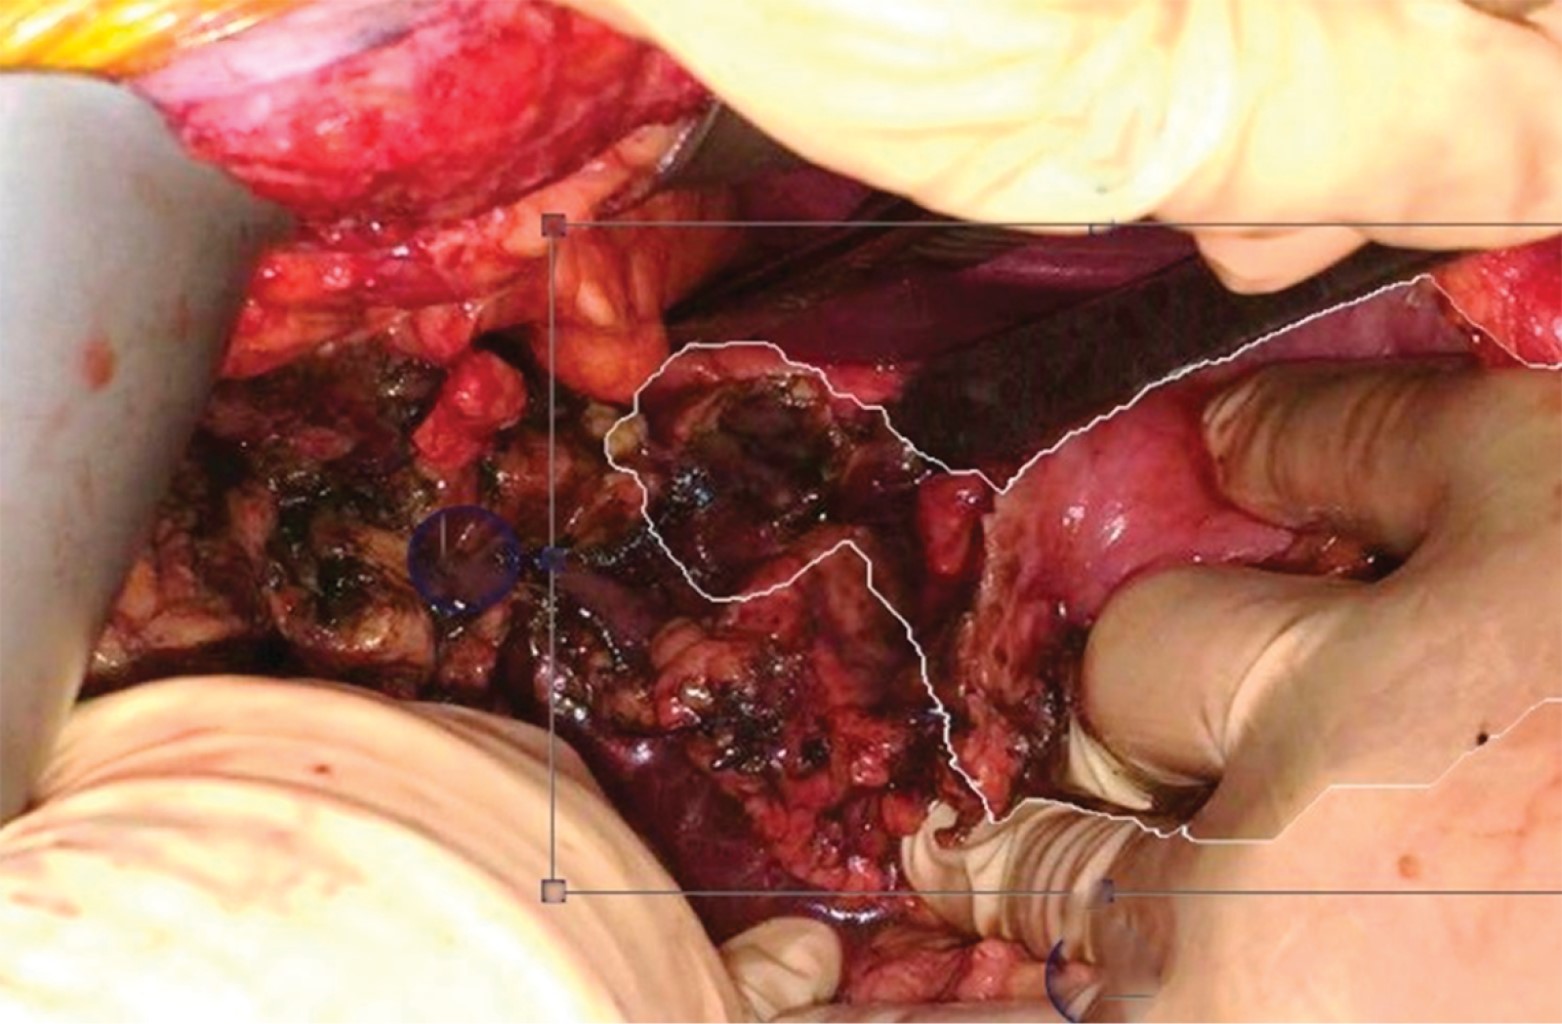

Se realizó laparotomía exploradora de urgencia, en la cual se evidenció la presencia de una úlcera duodenal circunferencial con sección completa de la primera porción del duodeno (Figura 2), abundante líquido biliar libre y en pozos de café; se realizó cierre de muñón duodenal con duodenostomía, antrectomía y derivación gastroyeyunal en omega de Braun manual con colocación de drenajes cerrados adyacentes a la anastomosis, con una duración del procedimiento de cuatro horas.

Figura 2